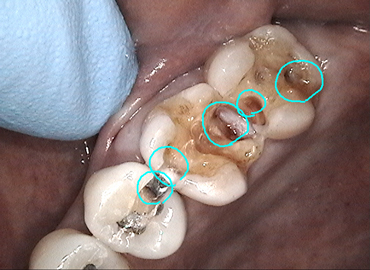

当院では「レントゲンで虫歯=青丸=の説明をされても実際よく分からない」という患者様の声を受けて、治療途中に虫歯の部分をビデオで記録します。その後、テレビモニターで虫歯の画像を患者様に確認してもらってから治療を続けています。

当院では、虫歯をビデオで撮影して患者様に報告しています。虫歯の存在を口で伝えるだけでなく、実際に見て確認して頂くことを目的にしています。

〈症例〉暗くて最も見えにくい上の奥歯もビデオで確認していただいています。